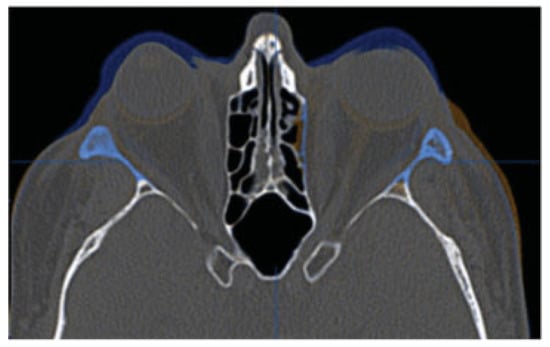

Three-month postoperative imaging demonstrated the bony removal and decompression of the orbital soft tissues (Figure 10). Virtual stereolithographic (Figure 11) and three-dimensional volumetric models were generated from the DICOM data and used for direct comparison of the pre- and postoperative orbits.

In the cases discussed herein, we routinely perform Hertel exophthalmometry as it is reproducible and easy to perform. After lateral rim removal, we clinically measure A-P globe position using the Naugle exophthalmometer; however, we do not have measurements with the Naugle preoperatively in these two cases. Rather, the reduction in proptosis in these two patients was easily verified on their pre- and postoperative CT scan fusion (Figure 5 and Figure 10). Objective outcome assessment utilizing the position of the anterior cornea to the orbital superior (Os) and orbitale inferior (Oi) is ongoing and will be the goal of future works.

Figure 10. Fusion of preoperative (blue) and postoperative (orange) CT scans for patient 2. Uncolored portions are identical on the two scans.